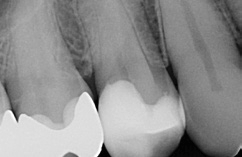

Bei dem 57-jährigen Patienten imponierte in der Routine-Bissflügelaufnahme eine Sekundärkaries an dem mit einem Gold-inlay versorgten Zahn 14 (Abb. 1). Der vitale und symptomfreie Zahn zeigte lediglich radiologisch (Abb. 2) einen Randdefekt distal sowie den Verdacht auf Karies unter dem Befestigungs- bzw. Unterfüllungszement. Nach Entfernung des Goldinlays ergab sich der Verdacht auf eine Pulpaeröffnung (Abb. 3). Klinisch war keine Blutung feststellbar, was allerdings durch die Lokalanästhesie kaschiert sein konnte. Aufgrund der Symptomlosigkeit des Zahnes und fehlender Anzeichen einer Pulpitis (fehlende Blutung) sowie einer Nekrose (erhaltene Vitalität) fiel die Entscheidung zugunsten einer Vitalerhaltung unter Beibehaltung eines engmaschigen Recalls mit Vitalitätsproben. Die Überkappung der Eröffnungsstellen erfolgte als Alternative zu Calciumhydroxid [8] mit einem Portlandzement enthaltenden Flowkomposit mit hohem pH-Wert [7,51] (TheraCal LC, Bisco, Abb. 4). Obwohl dieses Produkt hinsichtlich seiner Effektivität und Zelltoxizität nicht an ProRoot MTA (Dentsply Sirona) und Biodentine (Septodont) [42] herankommt [5,11], ist es hinsichtlich seiner Praktikabilität und der Möglichkeit des sofortigen, zügigen Weiterarbeitens konkurrenzlos. Ein vergleichbares Produkt gibt es z.B. bei Ultradent (Ultra- Blend Plus).